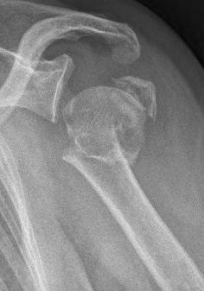

Proximaler Oberarmbruch3Proximaler Oberarmbruch4

Picture: The subcapital humeral fracture shown here in the axis is not broken and only slightly bruised, so that a conservative therapy is possible. The left image shows the follow-up after 3 weeks. The patient has already started physiotherapy. The x-ray shows an increase bone healing.